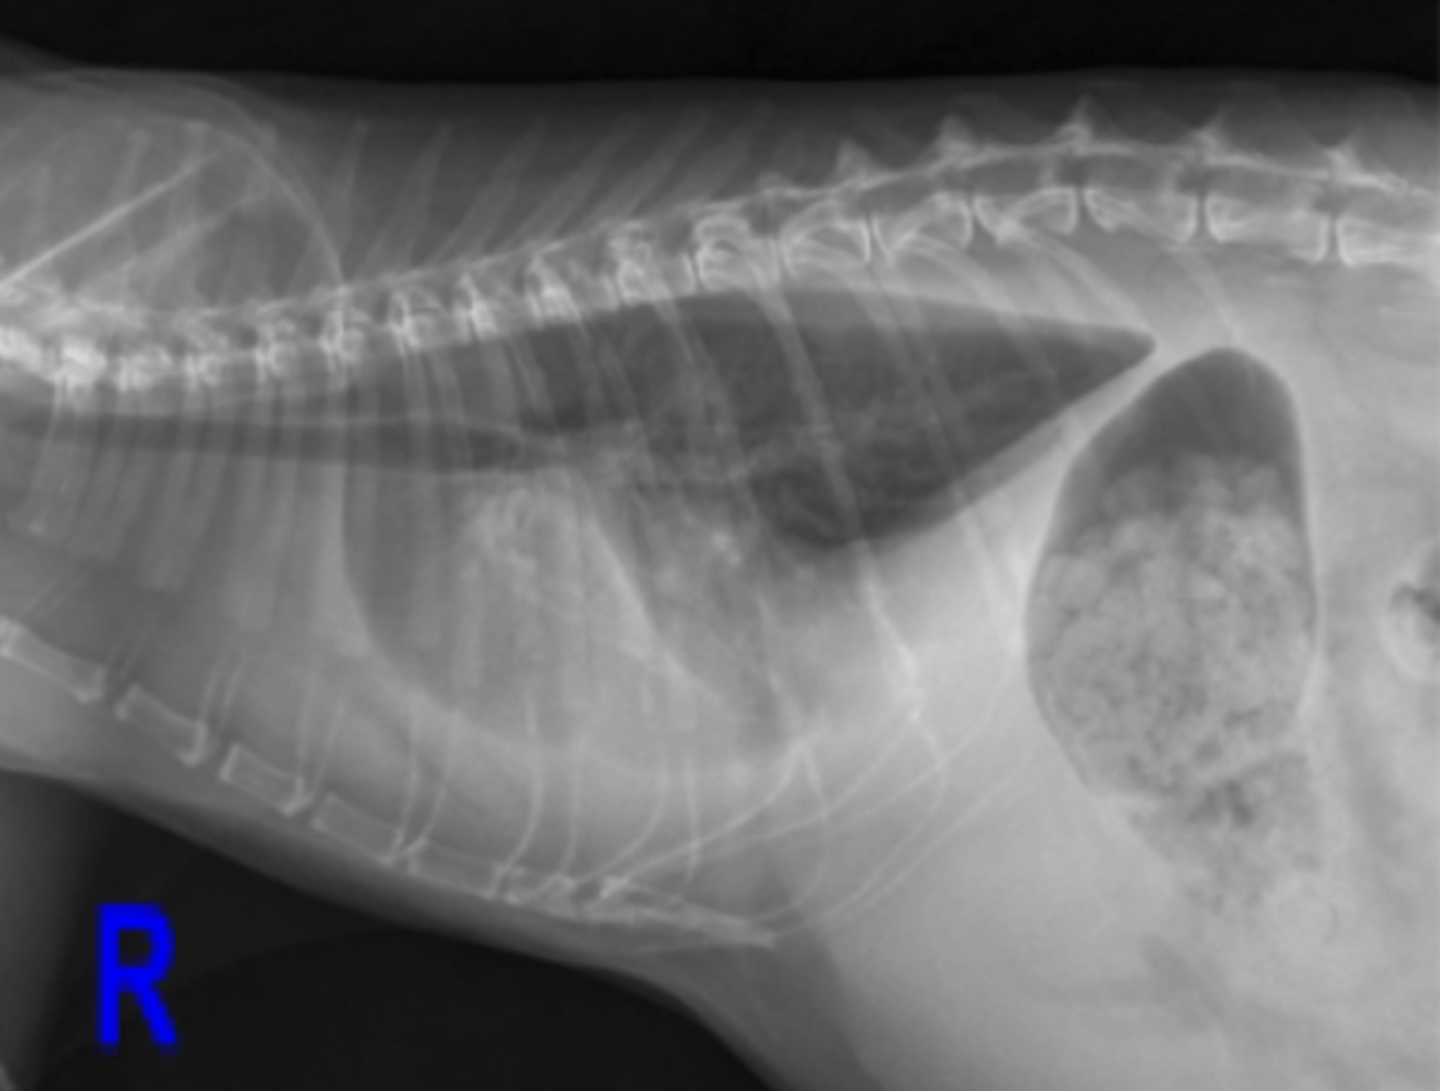

megacolon

patología: